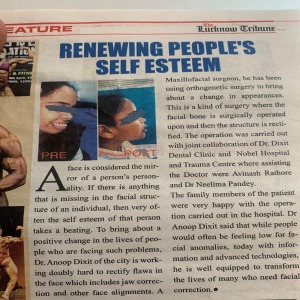

Dr. Anoop Dixit.

This clinic is running by Dr. Neelima Pandey Dixit & Team under the guidance of Dr. Anoop Dixit.

The clinic is equipped with all modern facility.